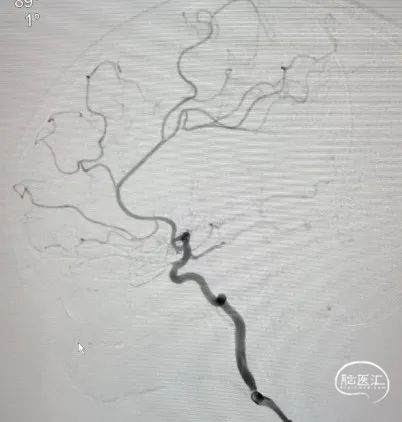

术前造影

1、微导管及微导丝引导下将6F 125cm Tethys®中间导引导管送至右侧颈内动脉床突段;

2、微导管及微导丝到达右侧大脑中动脉M2段中远端,撤出微导丝,手推造影确认位于M2血管真腔;

3、沿微导管缓慢释放3.0*25mm Syphonet®取栓支架;

4、跟进6F 125cm Tethys®中间导引导管越过大脑中病变处至右侧大脑中动脉M1段末端,负压状态下撤回3.0*25mm Syphonet®取栓支架至中间导管内,将Syphonet®取栓支架和Tethys®中间导引导管整体撤出。

术后造影